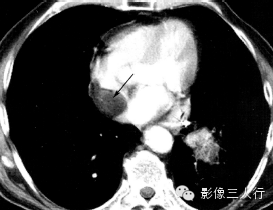

| 心房黏液瘤(图1) | 纤维瘤(图2) | 脂肪瘤(图3) | 横纹肌肉瘤(图4) | |

好发

年龄 |

成人 | 婴幼儿 | 成人 | 儿童或年轻人 |

部位 |

多起源于房间隔,以窄基底与其相连,并向心腔内生长 | 心室心肌内,常见于左室游离壁或室间隔 | 多原发于心外膜,在心房、心室无差异 | 各房室及间隔心肌壁均可发生,常累及一个以上心腔,可侵犯心包和大血管 |

病灶

形态 |

圆形或椭圆形,多呈浅分叶状,有蒂与心房间隔相连,肿瘤位置可随心动周期而变化,有时脱入左室 | 卵圆形或分叶状,常有薄层假薄膜,边界清楚 | 椭圆形或分叶状,边界清楚 | 形态不规则,边界不清,可见坏死、出血 |

CT

密度 |

稍低密度 | 密度稍低于心肌 | 脂肪密度 | 不均匀软组织密度 |

强化

特点 |

不均匀强化 | 强化程度较正常心肌弱 | 无强化 | 一般均匀强化,坏死后内部不强化 |